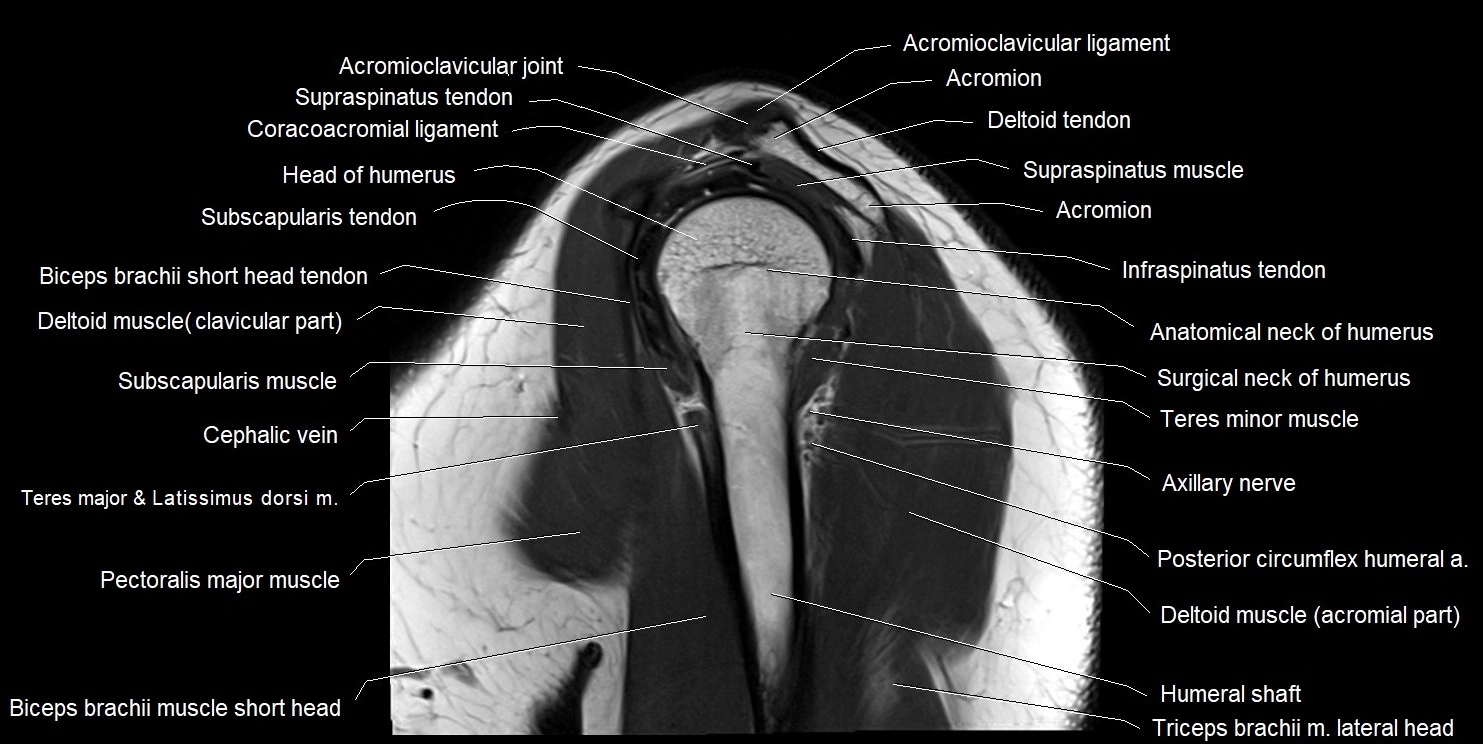

MRI images

image